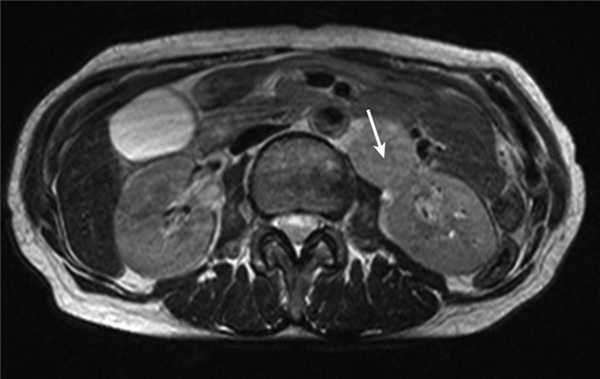

Медиана наблюдения пациенток группы сравнения составила 45,5 мес. За это время одна пациентка 64 лет была исключена из исследования в связи с летальным исходом в раннем послеоперационном периоде, возникшем на фоне ТЭЛА. В одном случае у больной 60 лет с диагнозом рак эндометрия IIA стадии (T2aNoMo) через 15 мес после окончания первичного лечения (операция с адъювантной сочетанной лучевой терапией) диагностирован рецидив заболевания: при контрольном обследовании в парааортальной зоне в области ворот левой почки выявлен конгломерат опухолевых узлов до 4 см (рис. 4). Рисунок 4. Рецидив опухоли в виде конгломерата лимфатических узлов в области ворот левой почки (стрелка) у больных группы сравнения.

Пациентке была выполнена повторная операция - парааортальная лимфаденэктомия. В качестве адъювантного противорецидивного лечения была проведена дистанционная лучевая терапия на эту зону с последующими курсами полихимиотерапии. В настоящее время пациентка жива, находится под наблюдением 6 мес без признаков прогрессирования заболевания.